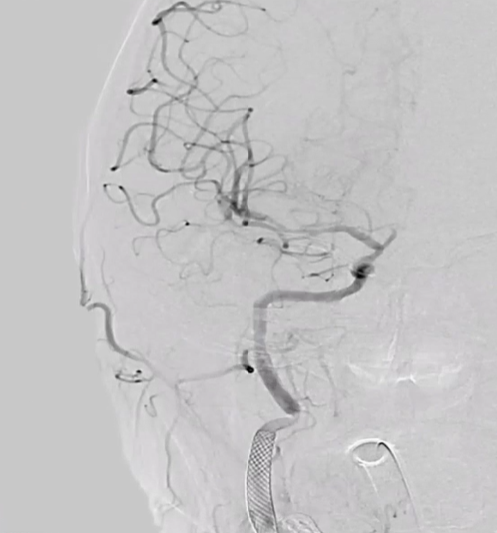

术前右侧椎动脉造影

病历夹什么径技·第152期|串联营病历夹:川陕大营_https://www.jmylbn.com_新闻资讯_第11张

病历夹什么径技·第152期|串联营病历夹:川陕大营_https://www.jmylbn.com_新闻资讯_第12张

病历夹什么径技·第152期|串联营病历夹:川陕大营_https://www.jmylbn.com_新闻资讯_第13张<<滑动查看下一张图片>>

术前左侧椎动脉造影